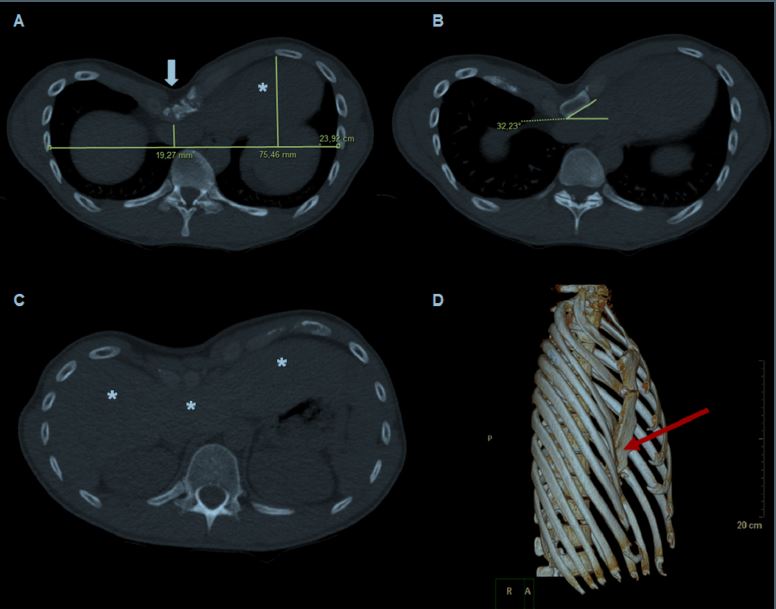

Resultados: Ofrecemos recomendaciones para la adquisición y análisis de imágenes preoperatorias, orientadas a la evaluación de la gravedad de la deformidad de la pared torácica (TC); el sitio de máxima compresión cardíaca, grado de aumento dependencia interventricular y presencia de derrame pericárdico (RMC); y el efecto de PEX en el funcional capacidad y función sistólica y / o diastólica relacionada con el ejercicio, y compresión del anillo tricúspide (Eco).